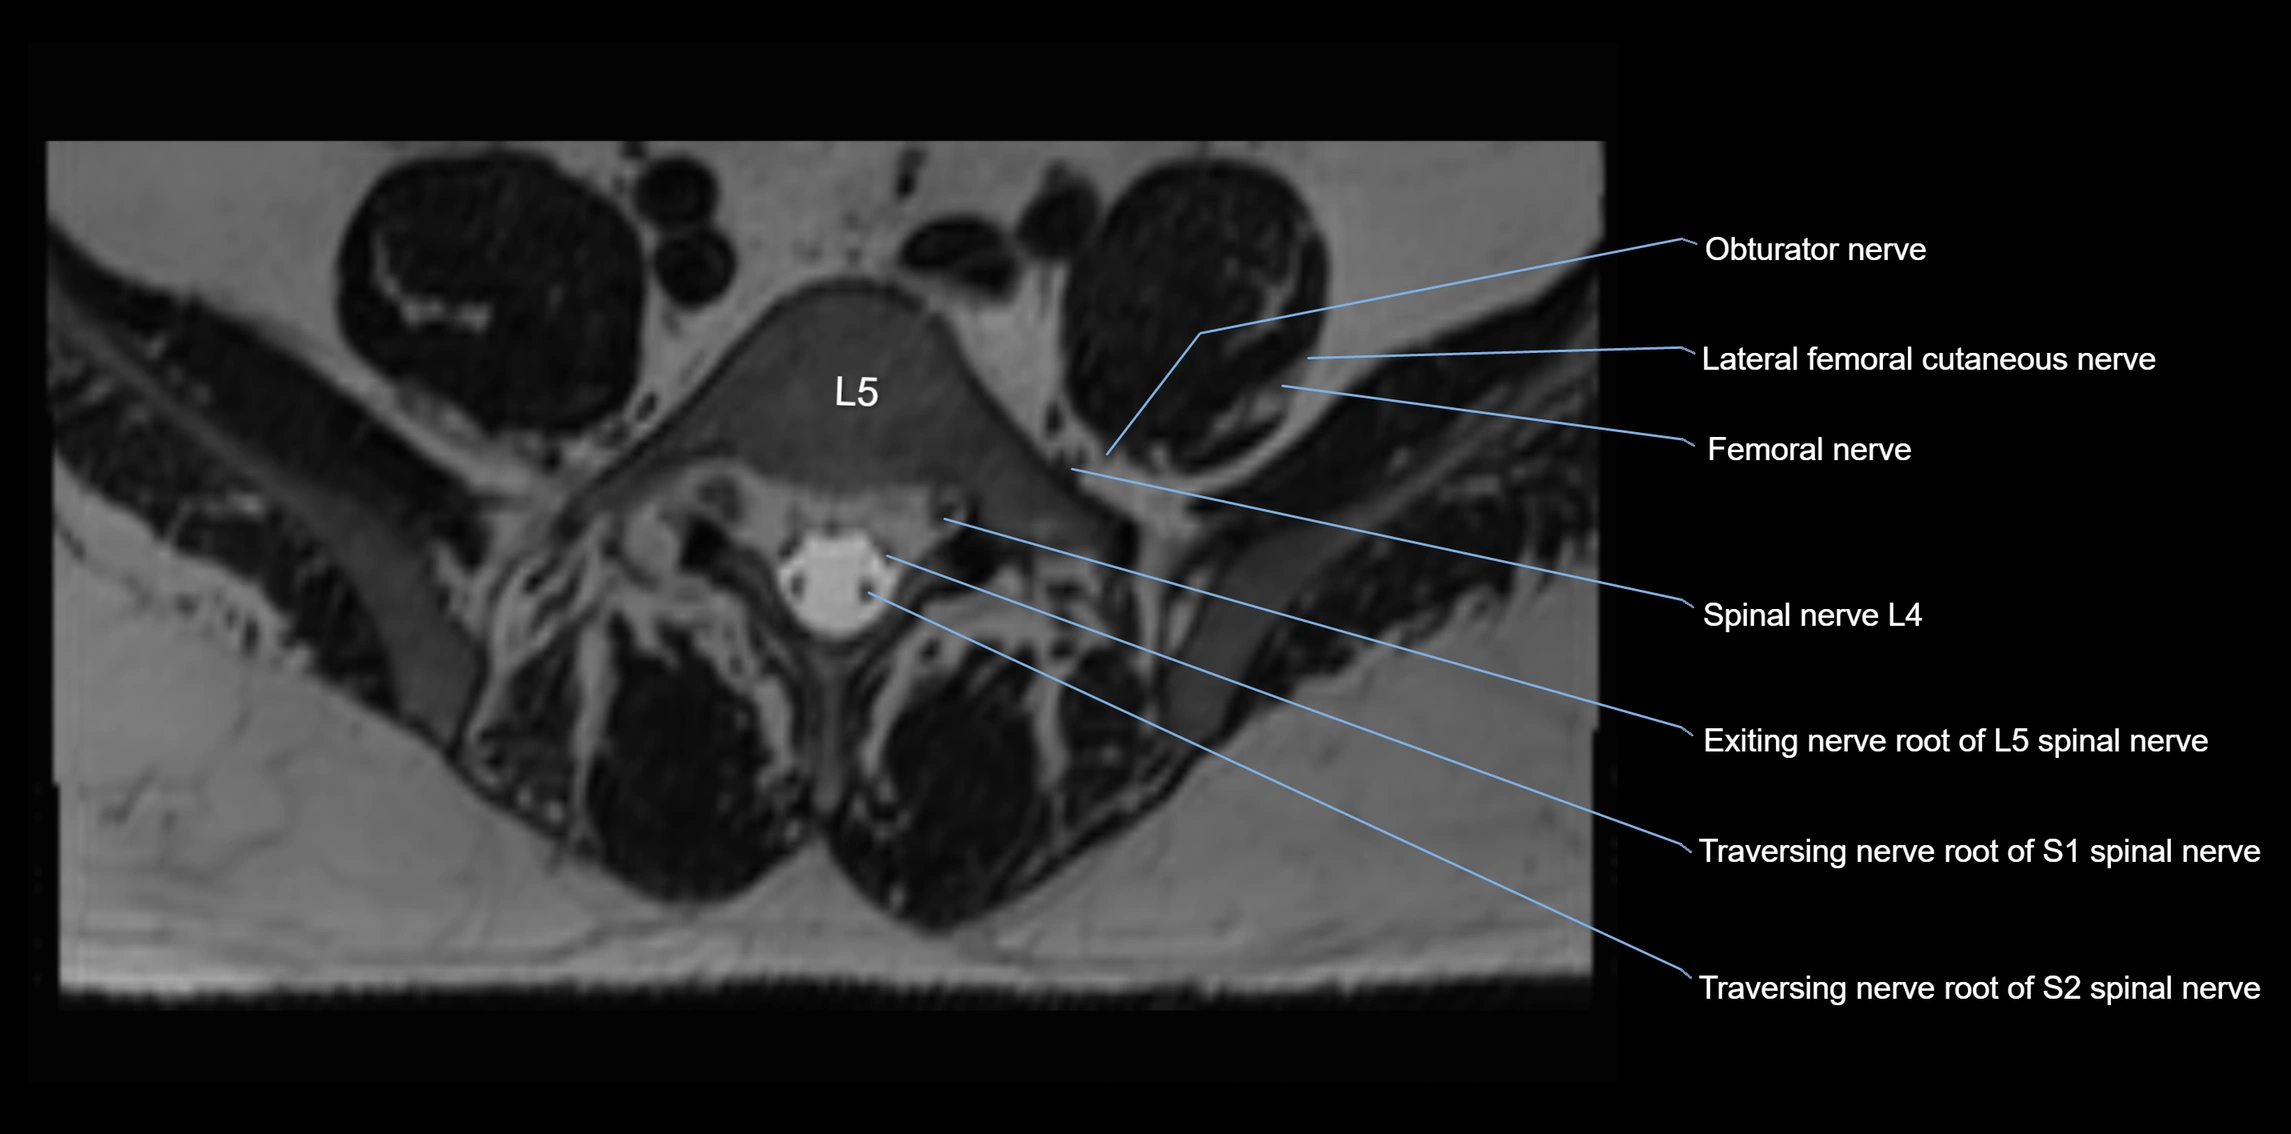

MRI image

image